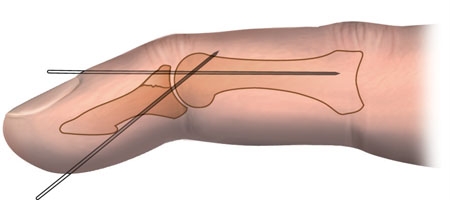

Alternativt kan operativ behandling foretages med K-tråds fiksation a.m Ishiguro eller med pull-outwire teknik. Efterbehandling

med castamskinne i 4 uger og siden i ergo-amb. til bevægeinstruktion.